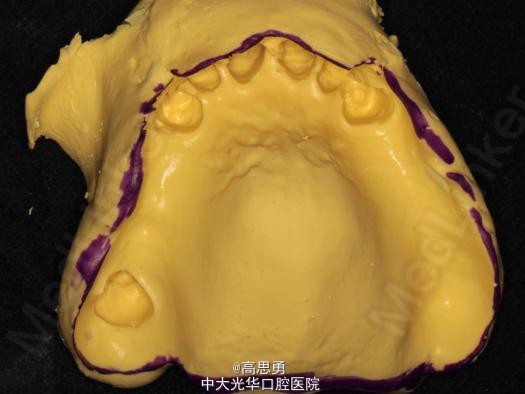

诊断: 1、牙列缺损(上颌肯氏II类I分类,下颌肯氏II类II分类) 2、#13慢性根尖周炎 3、#11、#12、#13、#21、#22、#23、#33、#42、#43、#44楔状缺损 4、慢性牙周炎 治疗计划 1、#13转牙体牙髓科做RCT 2、转牙体牙髓科对#11、#12、#13、#21、#22、#23、#33、#42、#43、#44楔状缺损 充填治疗 3、转牙周科进行牙周洁治 4、择期RPD修复 备选修复方案: 1、#13RCT后截冠后,上下颌覆盖义齿修复; 2、#13RCT后冠修复,上下颌可摘局部义齿修复; 3、#13RCT后树脂充填,上下颌可摘局部义齿修复; 4、#13拔除后,上下颌可摘局部义齿修复。 患者意愿:患者希望尽量保持#13的天然形态,要求费用尽量低,但能恢复正常咀嚼功能。 最终治疗方案:根据患者的年龄、身体状况、治疗周期、经济状况,患者最终选择方案5,即#13RCT后树脂充填,上颌结合卡环式可摘局部义齿修复;下颌可摘铸造支架式局部义齿修复。 治疗过程: 1、临床检查和#13树脂充填 对患者进行全面的口腔检查,用Z350树脂充填#13,调HE,抛光。 2、研究模型 调拌藻酸盐印模材料于2号成品托盘上取上下颌研究模,灌注石膏模型,研究分析、制定治疗计划,并制作个别托盘。 3、基牙预备 对#13近中、#23远中、#27近中、#34近中、#47近中常规制备支托凹,抛光。 4、工作模型 调拌藻酸盐印模材料于个别托盘上。做一定的边缘整塑,取上下颌研究模,灌注石膏模型。 5、试戴支架 检查支架的就位、固位可,无翘动,调HE,抛光,用蜡堤取颌位关系,上颌架,排牙,比色C4。 6、试排牙 检查义齿的就位、固位可,无翘动,观察人工牙的咬合状况,尖窝接触良好,正中颌位能重复,患者无诉不适,面容自然,外观满意。送加工厂充胶制作最终修复体。 7、试戴 检查义齿的就位、固位可,无翘动,咬合关系正确,利用咬合纸检查,上下颌尖窝接触均匀全面,抛光,患者表示满意,嘱注意事项,定期复诊。